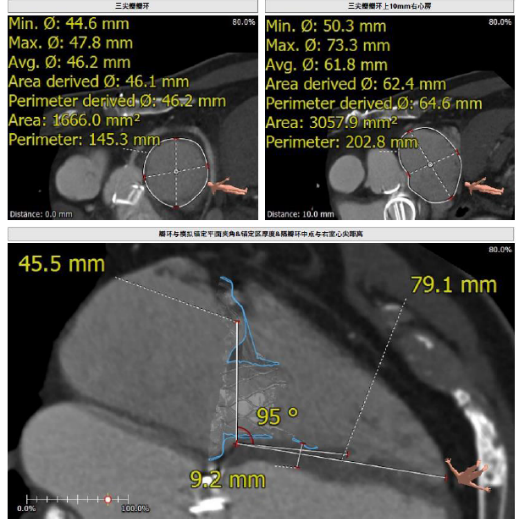

接受本次治療的是一例三尖瓣重度反流的患者,NYHA心功能Ⅲ級。主訴“反復(fù)活動后氣促1年,下肢水腫4個月”。入院N末端B型腦鈉肽前體(NT-proBNP)3161pg/ml。心電圖提示:心房顫動,ST-T改變。術(shù)前超聲提示:重度三尖瓣關(guān)閉不全,右心房擴(kuò)大,三尖瓣收縮期位移(TAPSE)14mm,左房增大,左室收縮功能正常低值,主動脈瓣、二尖瓣機(jī)械瓣功能良好。術(shù)前CT評估(圖1):三尖瓣瓣環(huán)(周長換算直徑)大小為46.2mm;入路血管無嚴(yán)重迂曲,無鈣化;雙側(cè)冠脈有鈣化。